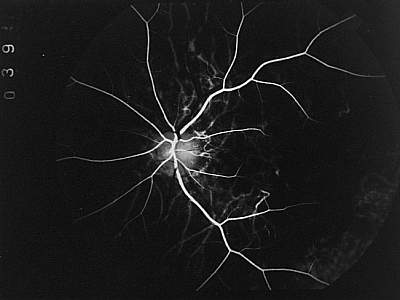

Abb. 13 Phase der Füllung der großen Aderhautgefäße (FLADOP, IOD = 68 mmHg) |

Entsprechend der Anatomie der Aderhaut füllen sich bei hohen intraokularen Drucken zunächst nur die großen Aderhautgefäße der Haller'schen Schicht. Die Reihenfolge der Füllung dieser Gefäße ist von einer außerordentlichen Variabilität. Am häufigsten findet man die frühe Anfärbung von großen Aderhautgefäßen in der peripapillären Region. Die kurzen hinteren Ziliararterien scheinen hier in unmittelbarer Nachbarschaft zur Papille die Sklera zu durchdringen. Auf ihrem sternförmigen Verlauf zur Peripherie verzweigen sie sich mehrmals auf dichotome oder asymmetrische Art. Wie in Abb. 12 zu erkennen ist, stellt sich gelegentlich eine ringförmige arterielle Anastomose um die Papille dar. Sie entspricht dem Zinn-Haller'schen Gefäßring. Unter der weiteren Abnahme des intraokularen Drucks treten nun weitere große Aderhautgefäße an unterschiedlichen Stellen des hinteren Pols in Erscheinung. Ihre langsame Füllung mit Fluoreszein erlaubt den Durchtritt durch die Sklera sowie den weiteren Gefäßverlauf genau zu lokalisieren. Die frühe peripapilläre Füllung der Haller'schen Gefäßschicht ist jedoch nicht obligat. Ebenso kann beobachtet werden, daß sich zunächst verschiedene Gefäßstämme in der mittleren Peripherie anfärben, während sich die peripapillären Gefäße mit Verzögerung füllen (Abb. 13) . |